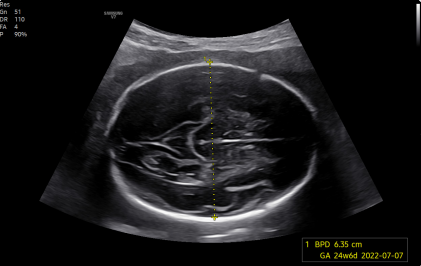

El Samsung V7 incorpora Crystal Architecture™, una plataforma de imagen avanzada que integra CrystalBeam™ y CrystalLive™, optimizada por sondas S-Vue™. Esta arquitectura permite imágenes más limpias, nítidas y de alta resolución, mejorando la confianza diagnóstica en obstetricia, ginecología, cardiología y aplicaciones generales.

CrystalBeam™ mejora la resolución y uniformidad de imagen mediante formación avanzada de haces, incluso en estructuras profundas o difíciles de visualizar.